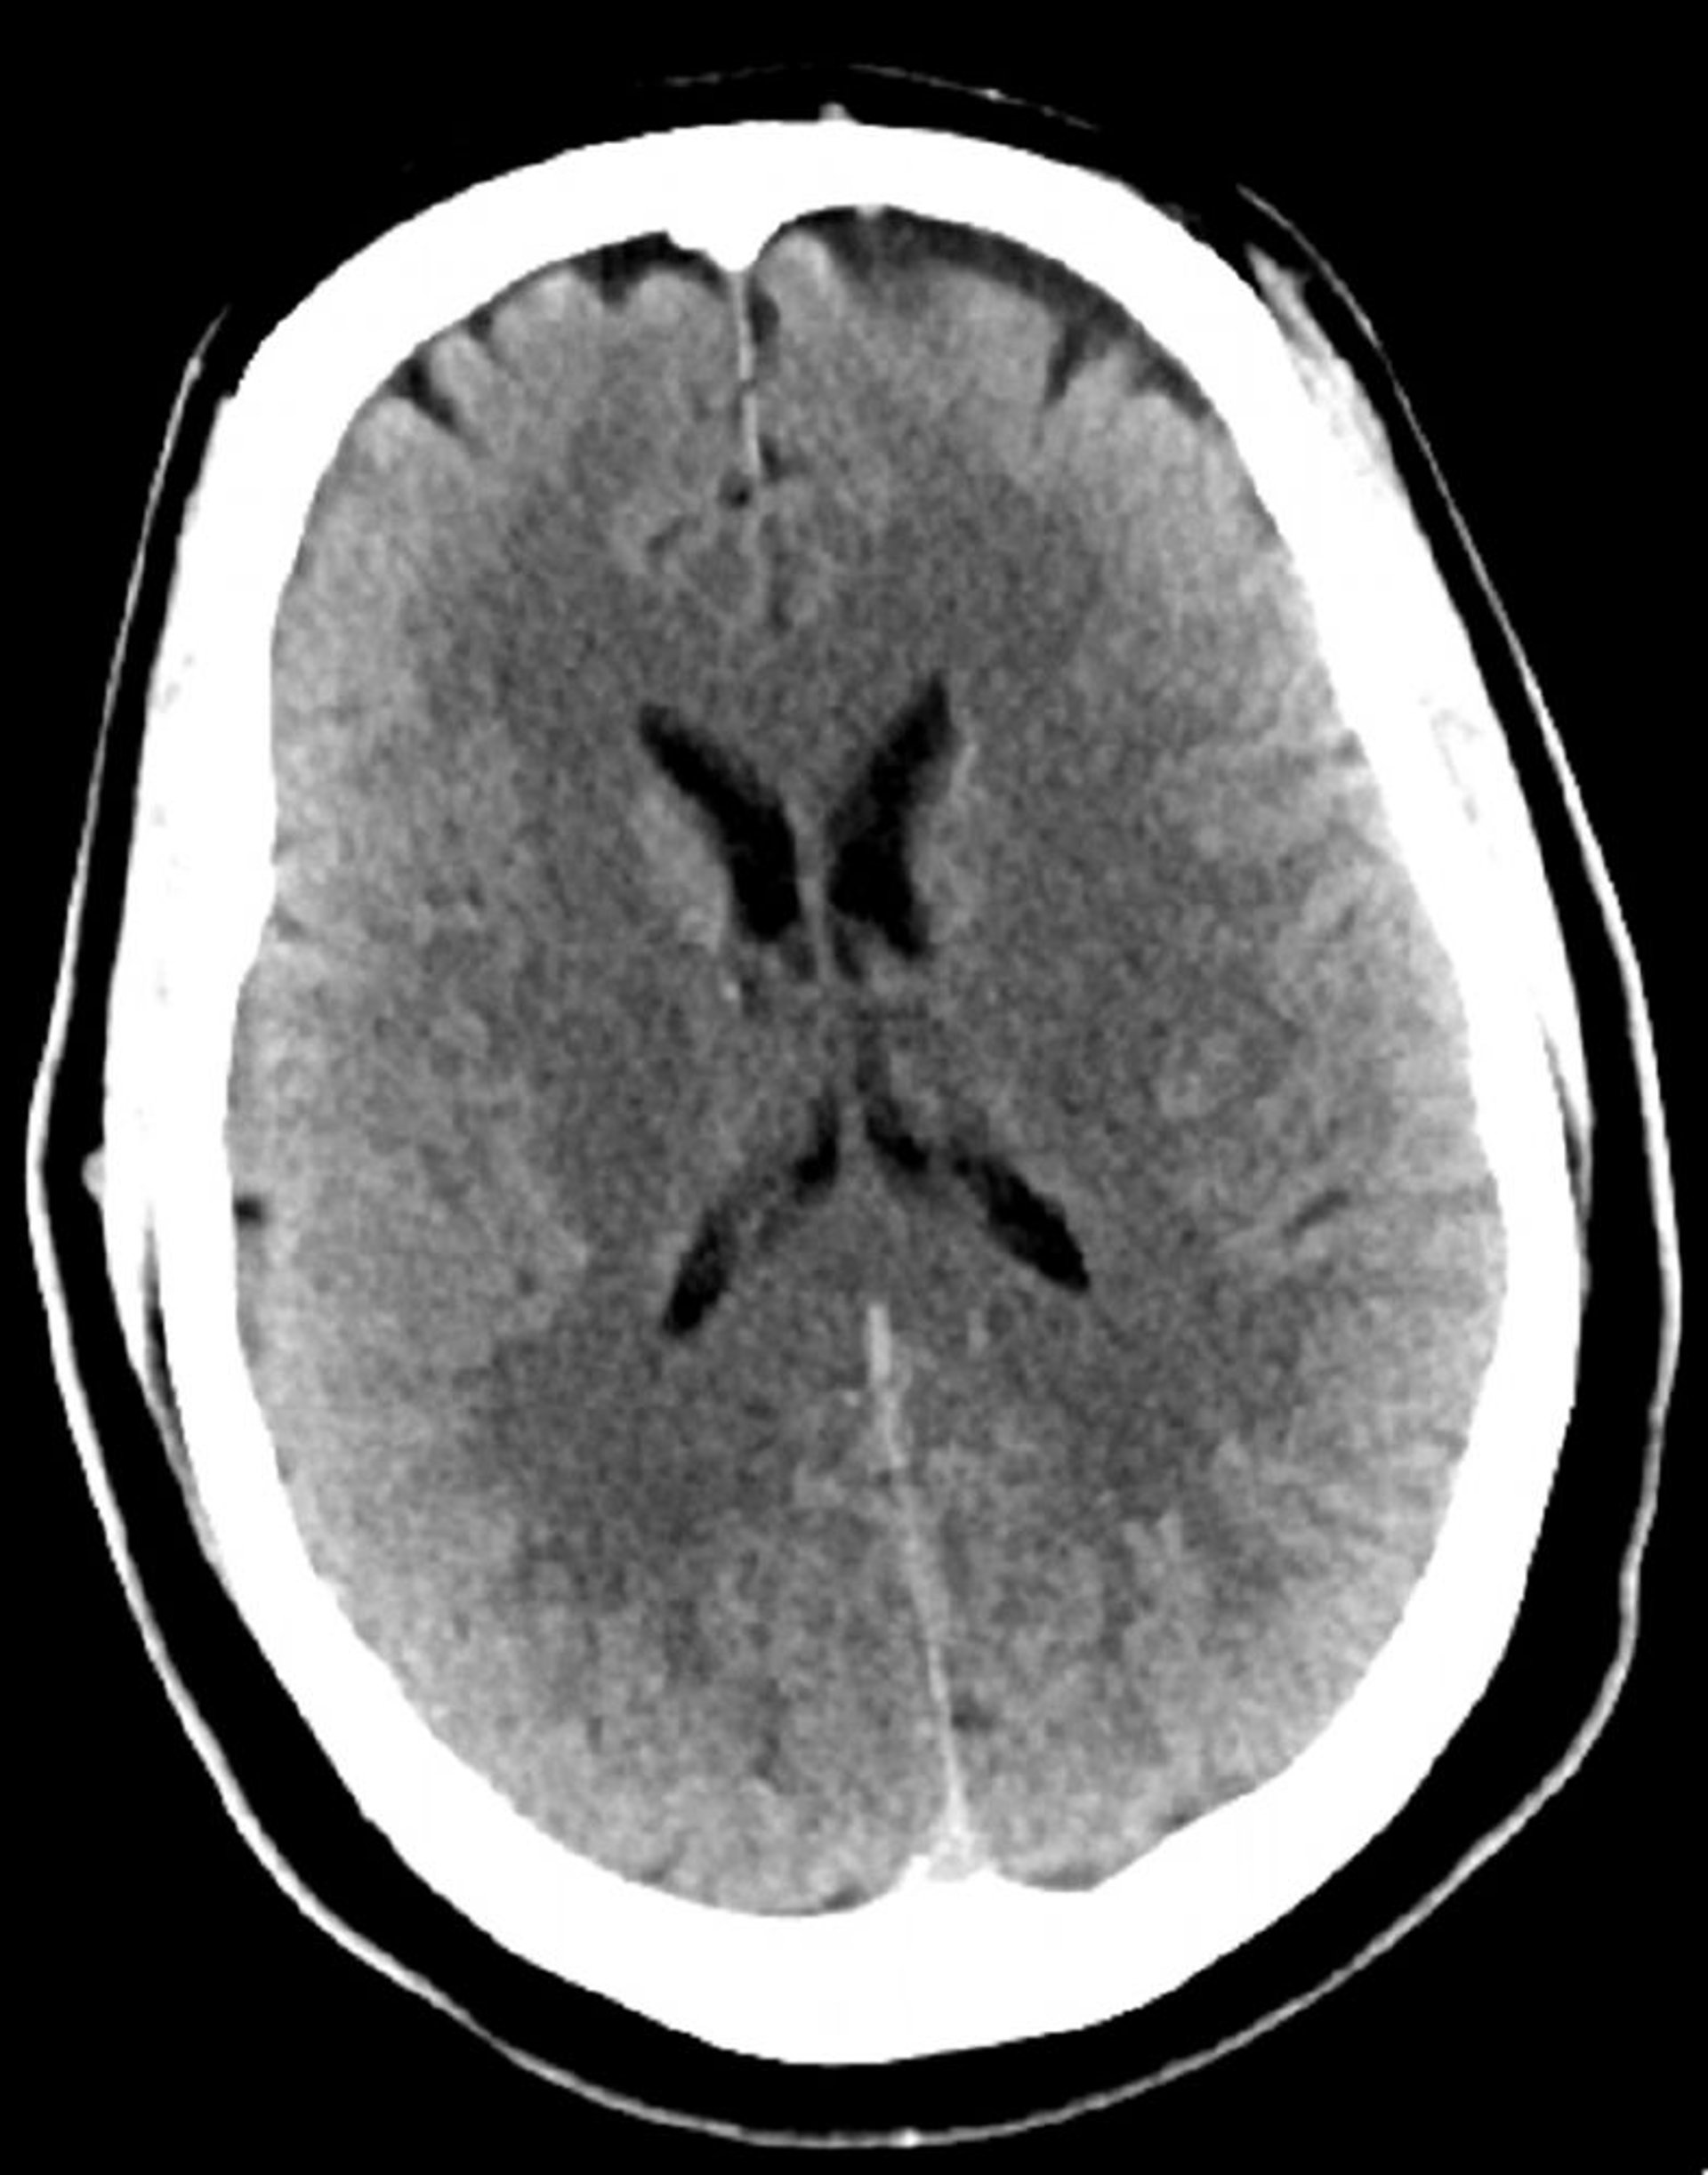

Chụp CT đầu bình thường (người lớn, 30 tuổi) – Lát cắt 4

Hình ảnh này là hình ảnh chụp CT đầu bình thường của một thanh niên 30 tuổi. Không có dịch hoặc xuất huyết trong hoặc ngoài trục. Gianh giới chất xám - chất trắng bảo toàn. Kích thước não thất và dạng khe bình thường.